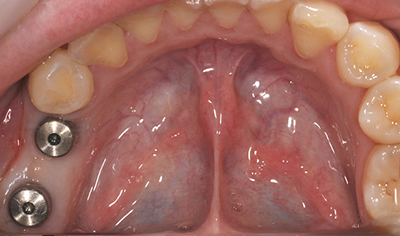

サージカルガイドを使えば、患者さまの状態によっては歯茎を切開しない手術が可能になることもあります。これにより低侵襲でインプラント治療を受けることができるため、患者さまに喜ばれることも多いです。

インプラントの症例